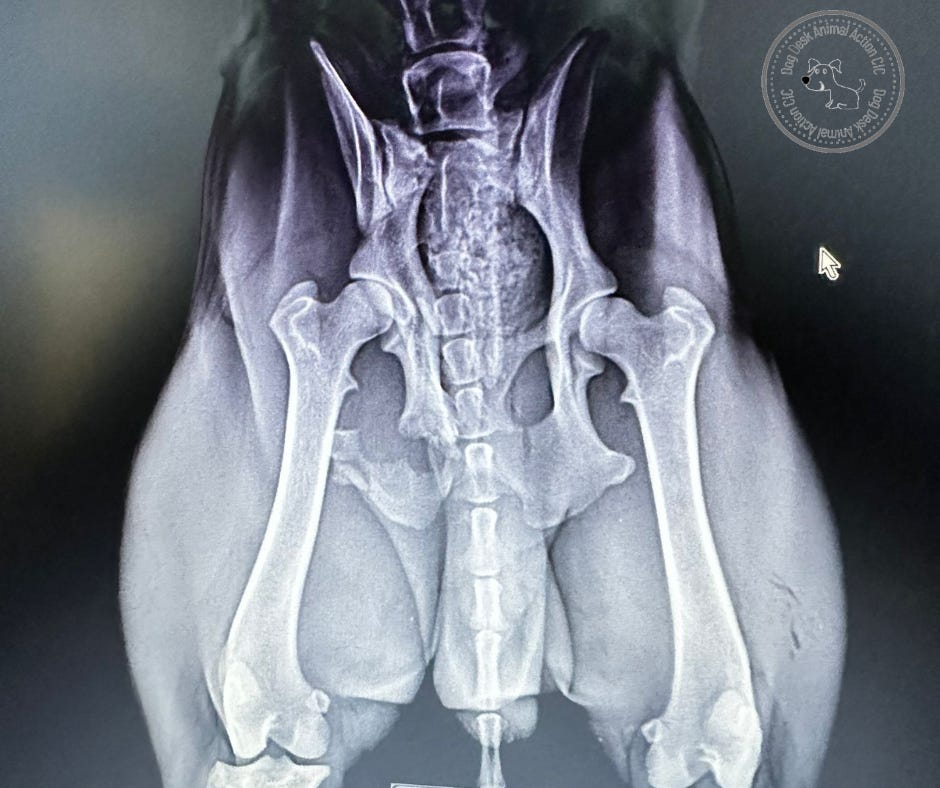

Calum had an obvious injury to one leg. He was holding it up, unable to bear weight with paw curled. I don’t know if there is any science in my observation but whenever I see this the dogs have had a broken pelvis.

X-rays revealed what we suspected. Calum had a fractured hip which needed immediate intervention.